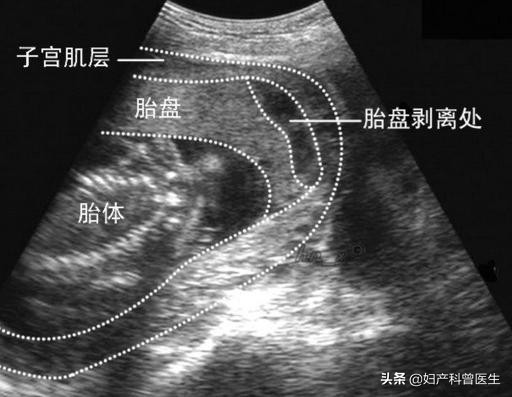

胎盘早剥

胎盘早剥B超图

胎盘早剥是指妊娠20周后或分娩期,正常位置的胎盘在胎儿娩出前,部分或全部从子宫壁剥离。发病率在国外为1%~2%,我国为0.46%~2.1%。它是妊娠晚期的一种严重并发症,往往发病急,进展快,如处理不及时,可威胁母婴的生命。宋运萍就是因为到医院的路途遥远,耽误了最佳抢救时间,大出血休克导致“一尸两命”。